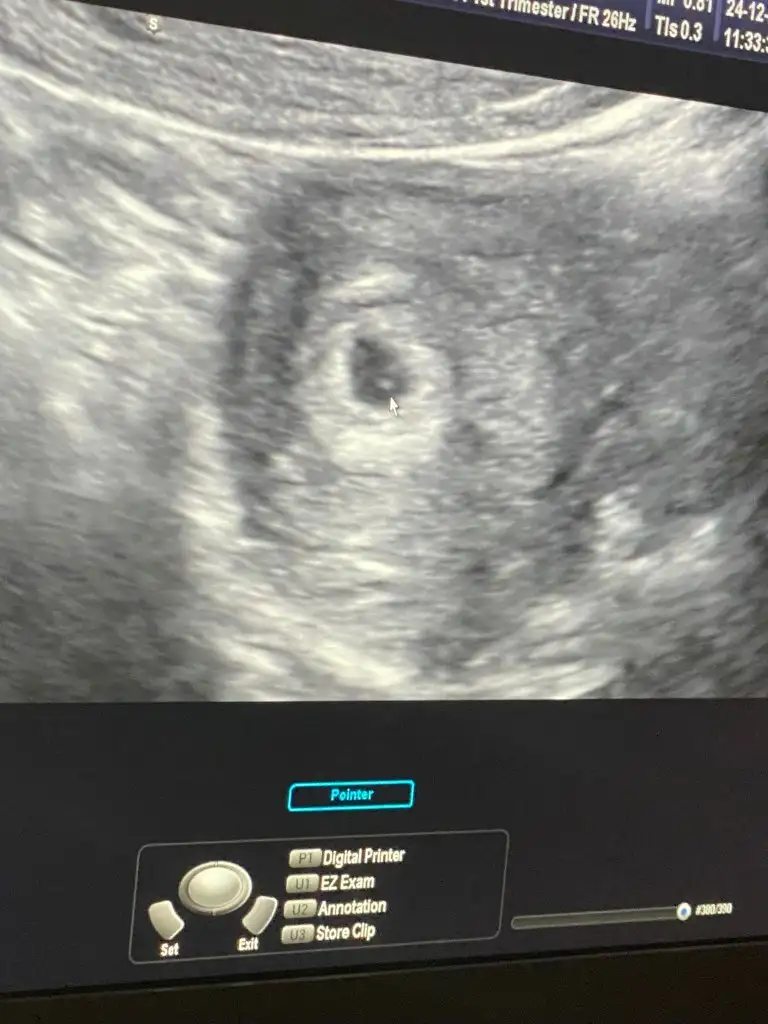

benm kesemi doktor 4+5 de görmüştü bet< değerim 2435 diKızlar kızlar,kese kaçıncı haftada gözüküyor?

5.hafta mi yoksa 6.hafta mi![]()

Şuan ben 4+6dayim beta hgcye 533den sonra baktirmadim.benm kesemi doktor 4+5 de görmüştü bet< değerim 2435 di

Benmde 4+5 te karından gördü kuzum icinde nokta bile gözükmüştüKızlar kızlar,kese kaçıncı haftada gözüküyor?

Ufak gördük ama tam net olmadığı için cuma tekrar gideceğim![]()

Alla alla benim neden gözükmedi ya, baş parmağı kadar gördük ama gölge gibi net göremedik kafama takıldıBenmde 4+5 te karından gördü kuzum icinde nokta bile gözükmüştü

Benım böyle bir şeydi ilkAlla alla benim neden gözükmedi ya, baş parmağı kadar gördük ama gölge gibi net göremedik kafama takıldı![]()

Ay bunu gördük yaaa,parmaktan küçük kalıyormus benzetmem biraz büyük olduBenım böyle bir şeydi ilk

Bakalım en son geçen salı gördüm bidaha 9 haftalıkken görcem![]()

Ayyy yerim minicikkkkhem hümanın makinaları iyi değil, ondan da olabilir sen kendini üzüp yıpratma. anlık görmüş olmanız bile rahat nefes alabilmen için büyük sebep

ay ne kadar olmuşşşAyyy yerim minicikkkk